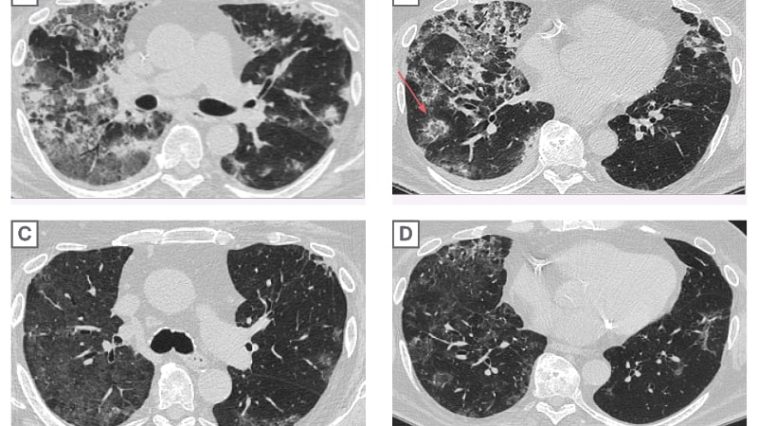

New Perspectives on Lung Cancer Treatment: The Role of Zongertinib The recent clinical trial spearheaded by Chinese and US scientists has generated considerable buzz in the medical community, introducing zongertinib as a promising new oral medication for treating HER2-mutated non-small cell lung cancer (NSCLC). Once considered a tricky area in lung cancer treatment, this new […] More